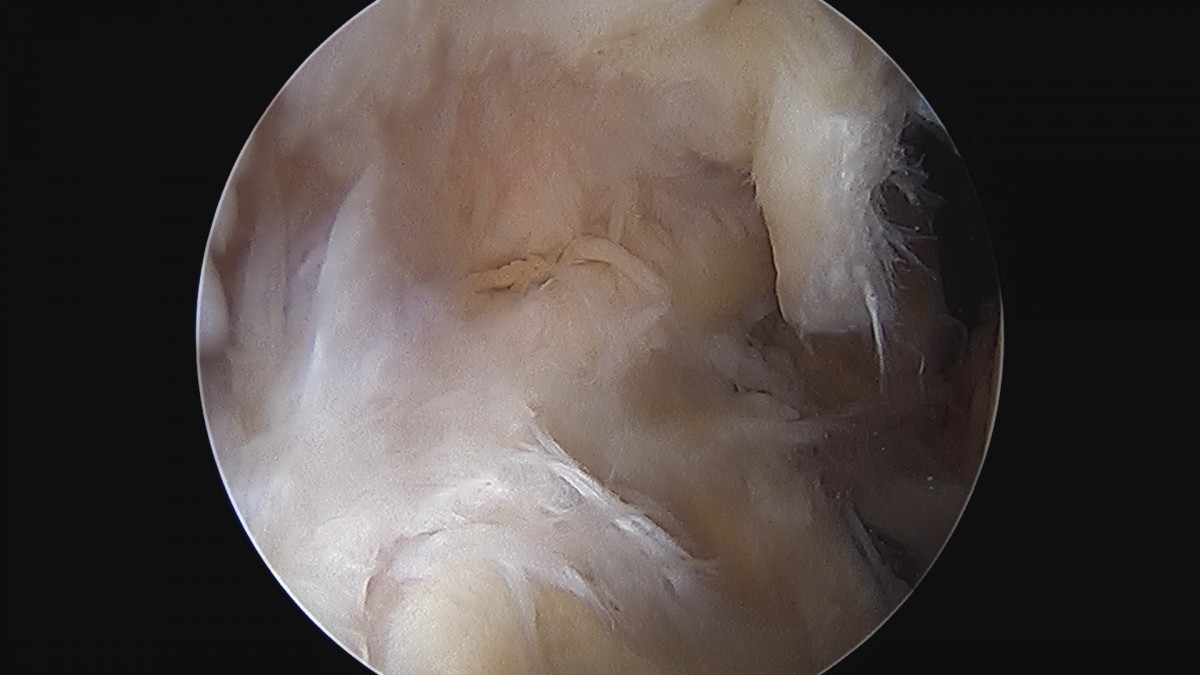

정지영원장님 어깨 회전근개 봉합술 임채O 환자

dae765e4d9ac96aee867c9d6292d8784_1758009112_4994.jpg